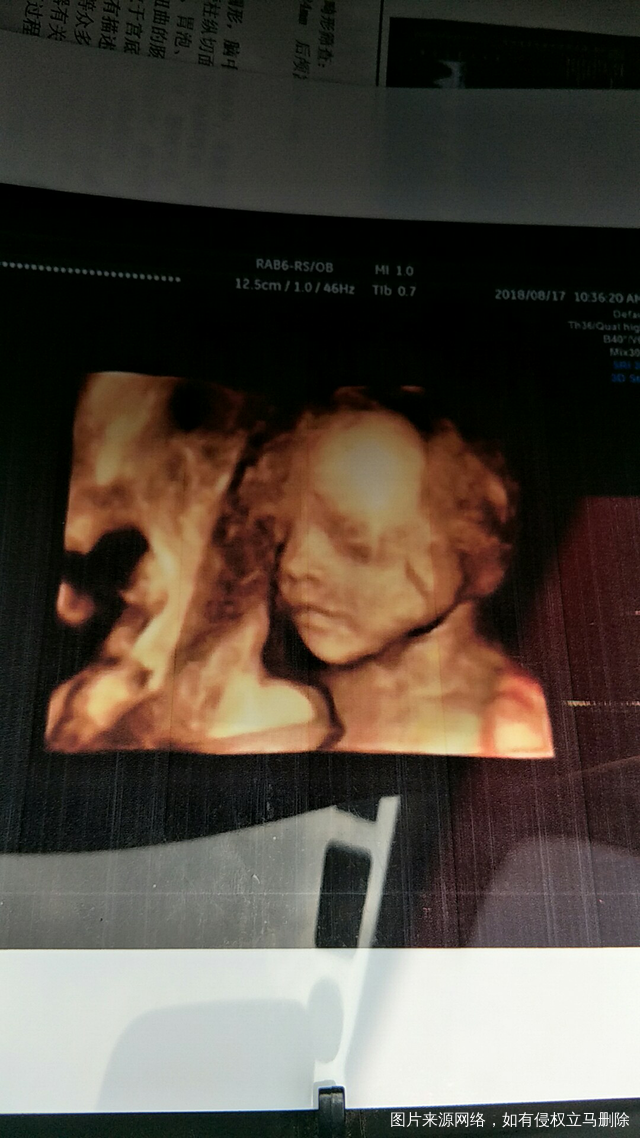

小天使👼

2018-08-17 13:13:40